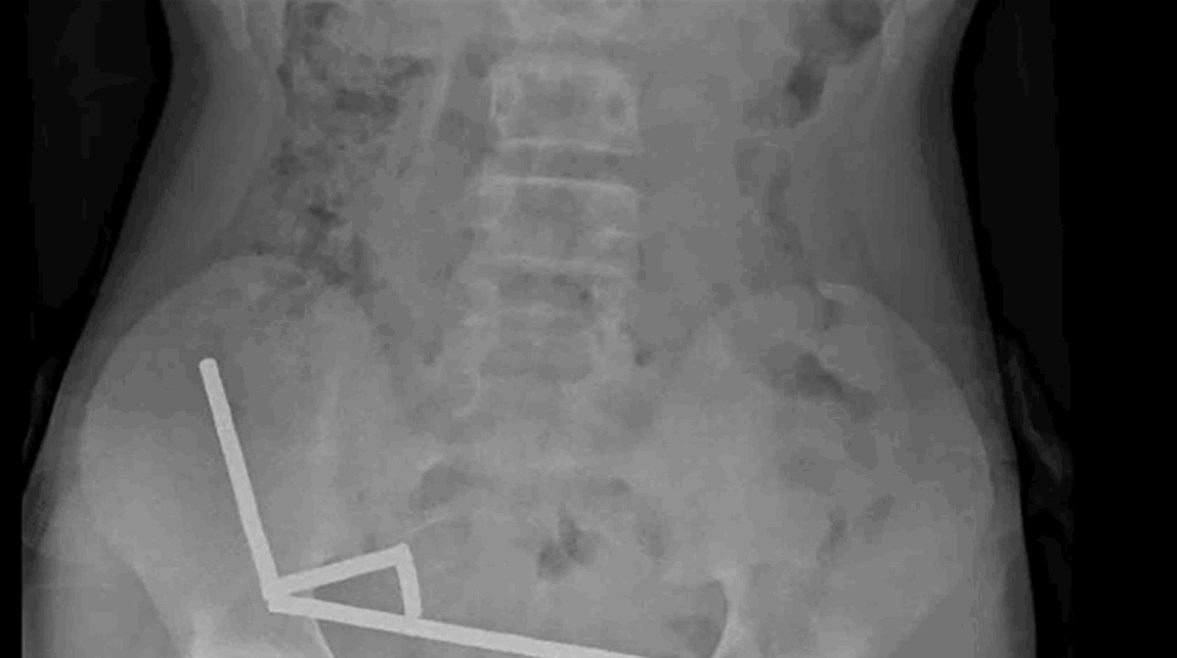

وقد تكتلت المغناطيسات معًا في أربعة خطوط مستقيمة داخل أمعاء الطفل، وكانت في أجزاء منفصلة من الأمعاء ملتصقة ببعضها البعض بسبب القوى المغناطيسية، وفقًا لما أظهرته الأشعة السينية.

وأشار الأطباء إلى أن ضغط المغناطيس تسبب في نخر الأنسجة في أربع مناطق من الأمعاء الدقيقة والأعور وهو جزء من الأمعاء الغليظة.